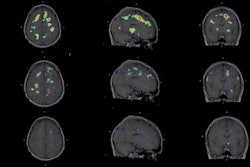

Myeliviz, developed by researchers at Case Western Reserve University, is designed to target and bind to the sheathing -- known as myelin -- that surrounds the nerves and is affected by MS. The tracers binding to myelin then can be visualized on PET images. By doing so, Myeliviz might provide evidence to help physicians determine the presence and degree of damage to patients' central nervous systems from MS.